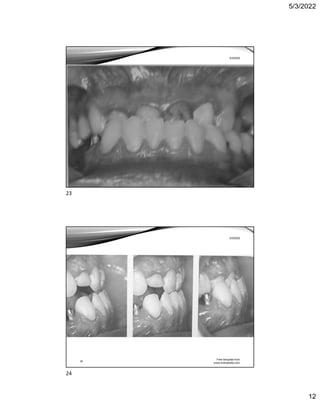

Figure 6.11 Upper and lower dental arch crowding.